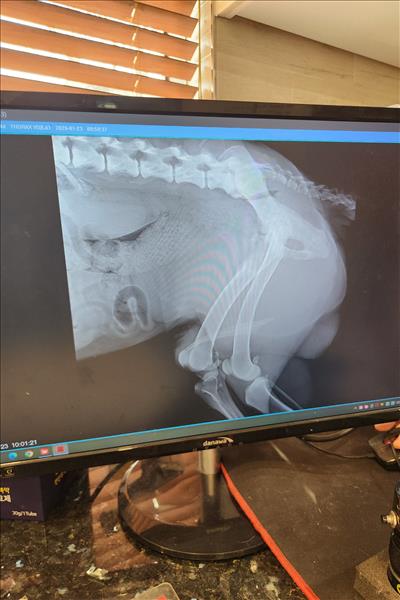

한달전에 자전거 산책이후 몇일후에 다리가 불편해 보여서 병원가서 소염진통제 처방받아서 먹이고 난뒤 몇일뒤 다리를 들기시작해서 병원가서 엑스레이도 찍었습니다. 지금 총기간이 한달정도 되었구요 미국 아키다 입니다. 체중은 40키로 정도이고요. 나이는 8.5살 정도 되는 수컷입니다. 왼쪽 다리입니다.

엑스레이 찍은 수의사님 말씀으론 뼈에는 아무 문제가 없다고 하네요.. 십자인대도 아무 문제 없다고 하시고.. 신경쪽 문제일수도 있다고 하시는대... 혹시나 다른병원을 가봐야 하는건지 너무 답답한 마음에 오늘 병원에 연락하여 엑스레이 사진 받아 왔습니다. 한번 봐주실수 있을까요. 부종같은건 없었는데 갑자기3일전부터 발바닥 조금위쪽 관절이 부종이 있는거같아요.. 만지면 불편해합니다. 갑자기 1달가까이 부종이없다가 부종이 생길수도 있나요??

그리고 몸이 한쪽으로 약간 틀어 진거같아요 다리를 들고있어서 그런건지...